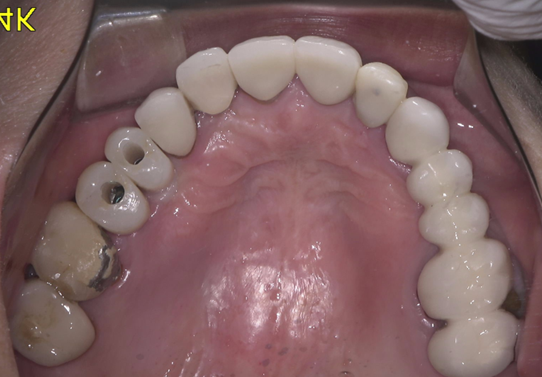

予定通りジルコニアクラウンにて、インプラント修復が行えました。

レントゲン写真でも理想的な位置

に埋入できました。